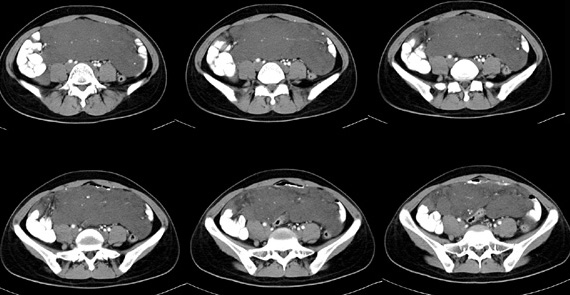

女性,28岁,停经3月,腹部膨隆1月,产前检查发现腹部占位

{肿块中心ct值27hu,增强后,动脉期、门脉期均无明显强化)

患者手术病理:腹腔囊性淋巴管瘤,象这样充满整个腹腔的的确很少见